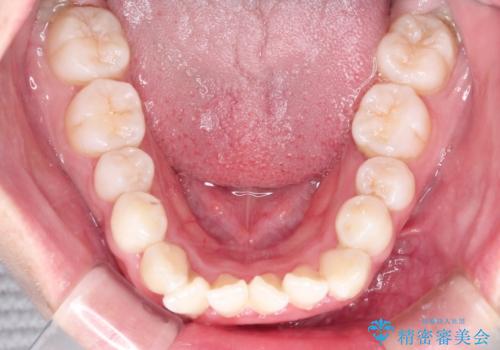

八重歯を改善!美しい口元を実現するハーフリンガル矯正

- 前歯のガタツキと口元のコンプレックスを解消するために来院されました。

ハーフリンガルワイヤー矯正で治療を開始しました。

ハーフリンガル矯正は、見た目を気にせずに矯正治療ができる方法です。この治療法は、八重歯や前歯のガタツキを効果的に改善します。特徴として、ワイヤーが上の歯の裏側に装着されるため、装置が外から見えません。これにより、治療中も自然な笑顔を保ちながら安心して治療を続けることができます。歯並びの悩みを持つ方にとって、非常に魅力的な選択肢です。